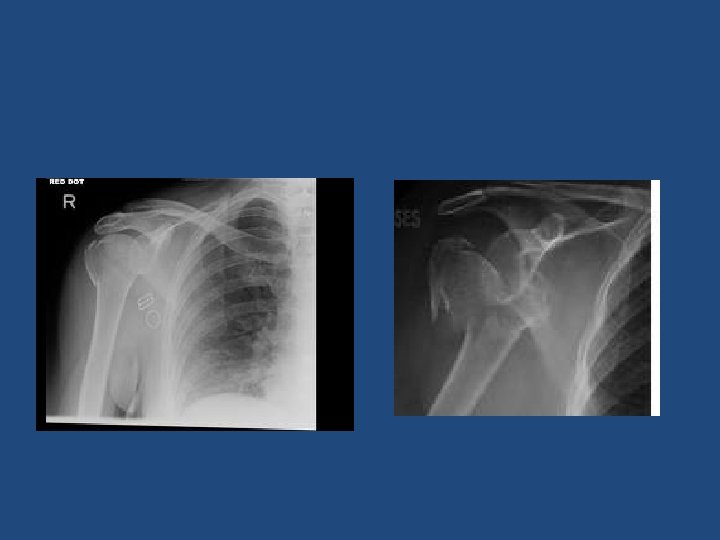

X-rays • AP, lateral and axillary views.